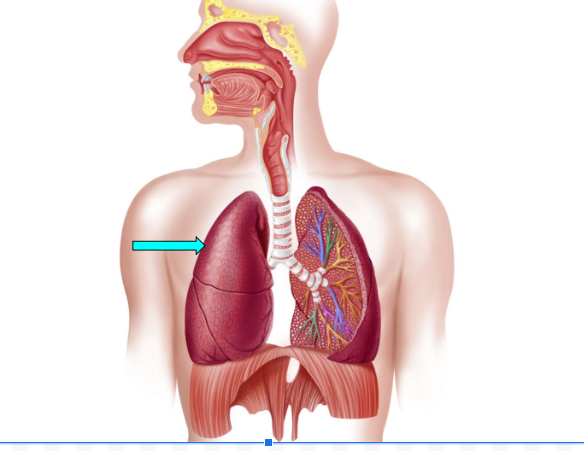

Right Lung

Right Lung (pic)